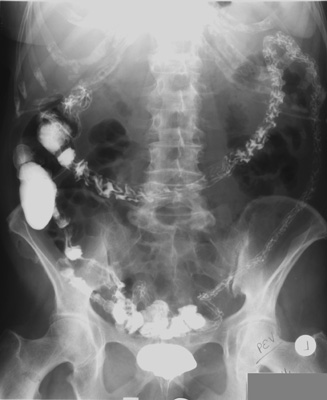

Single Contrast Barium Enema (cont.)

Overhead Radiographs |

- PA view of colon to include rectum -

patient prone, perpendicular central ray, 14" x 17" cassette

- Post-evacuation radiograph - patient prone, PA

view, vertical central ray, 14" x 17" cassette